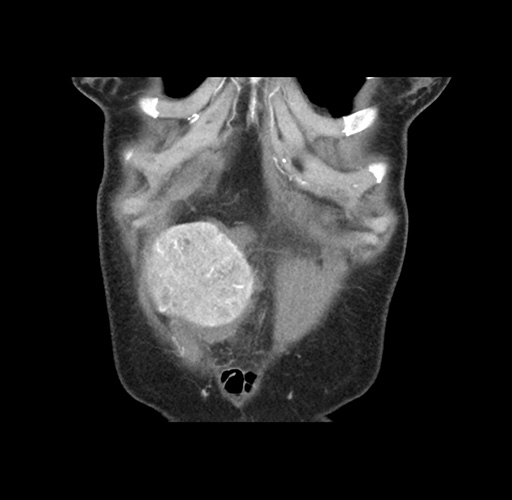

Imaging Analysis

Look through the patient's CT scan to identify any areas of concern for the necessary procedure.

Based on your CT findings, which issue(s) would give reason for "planned slowing down moment(s)" in this case?